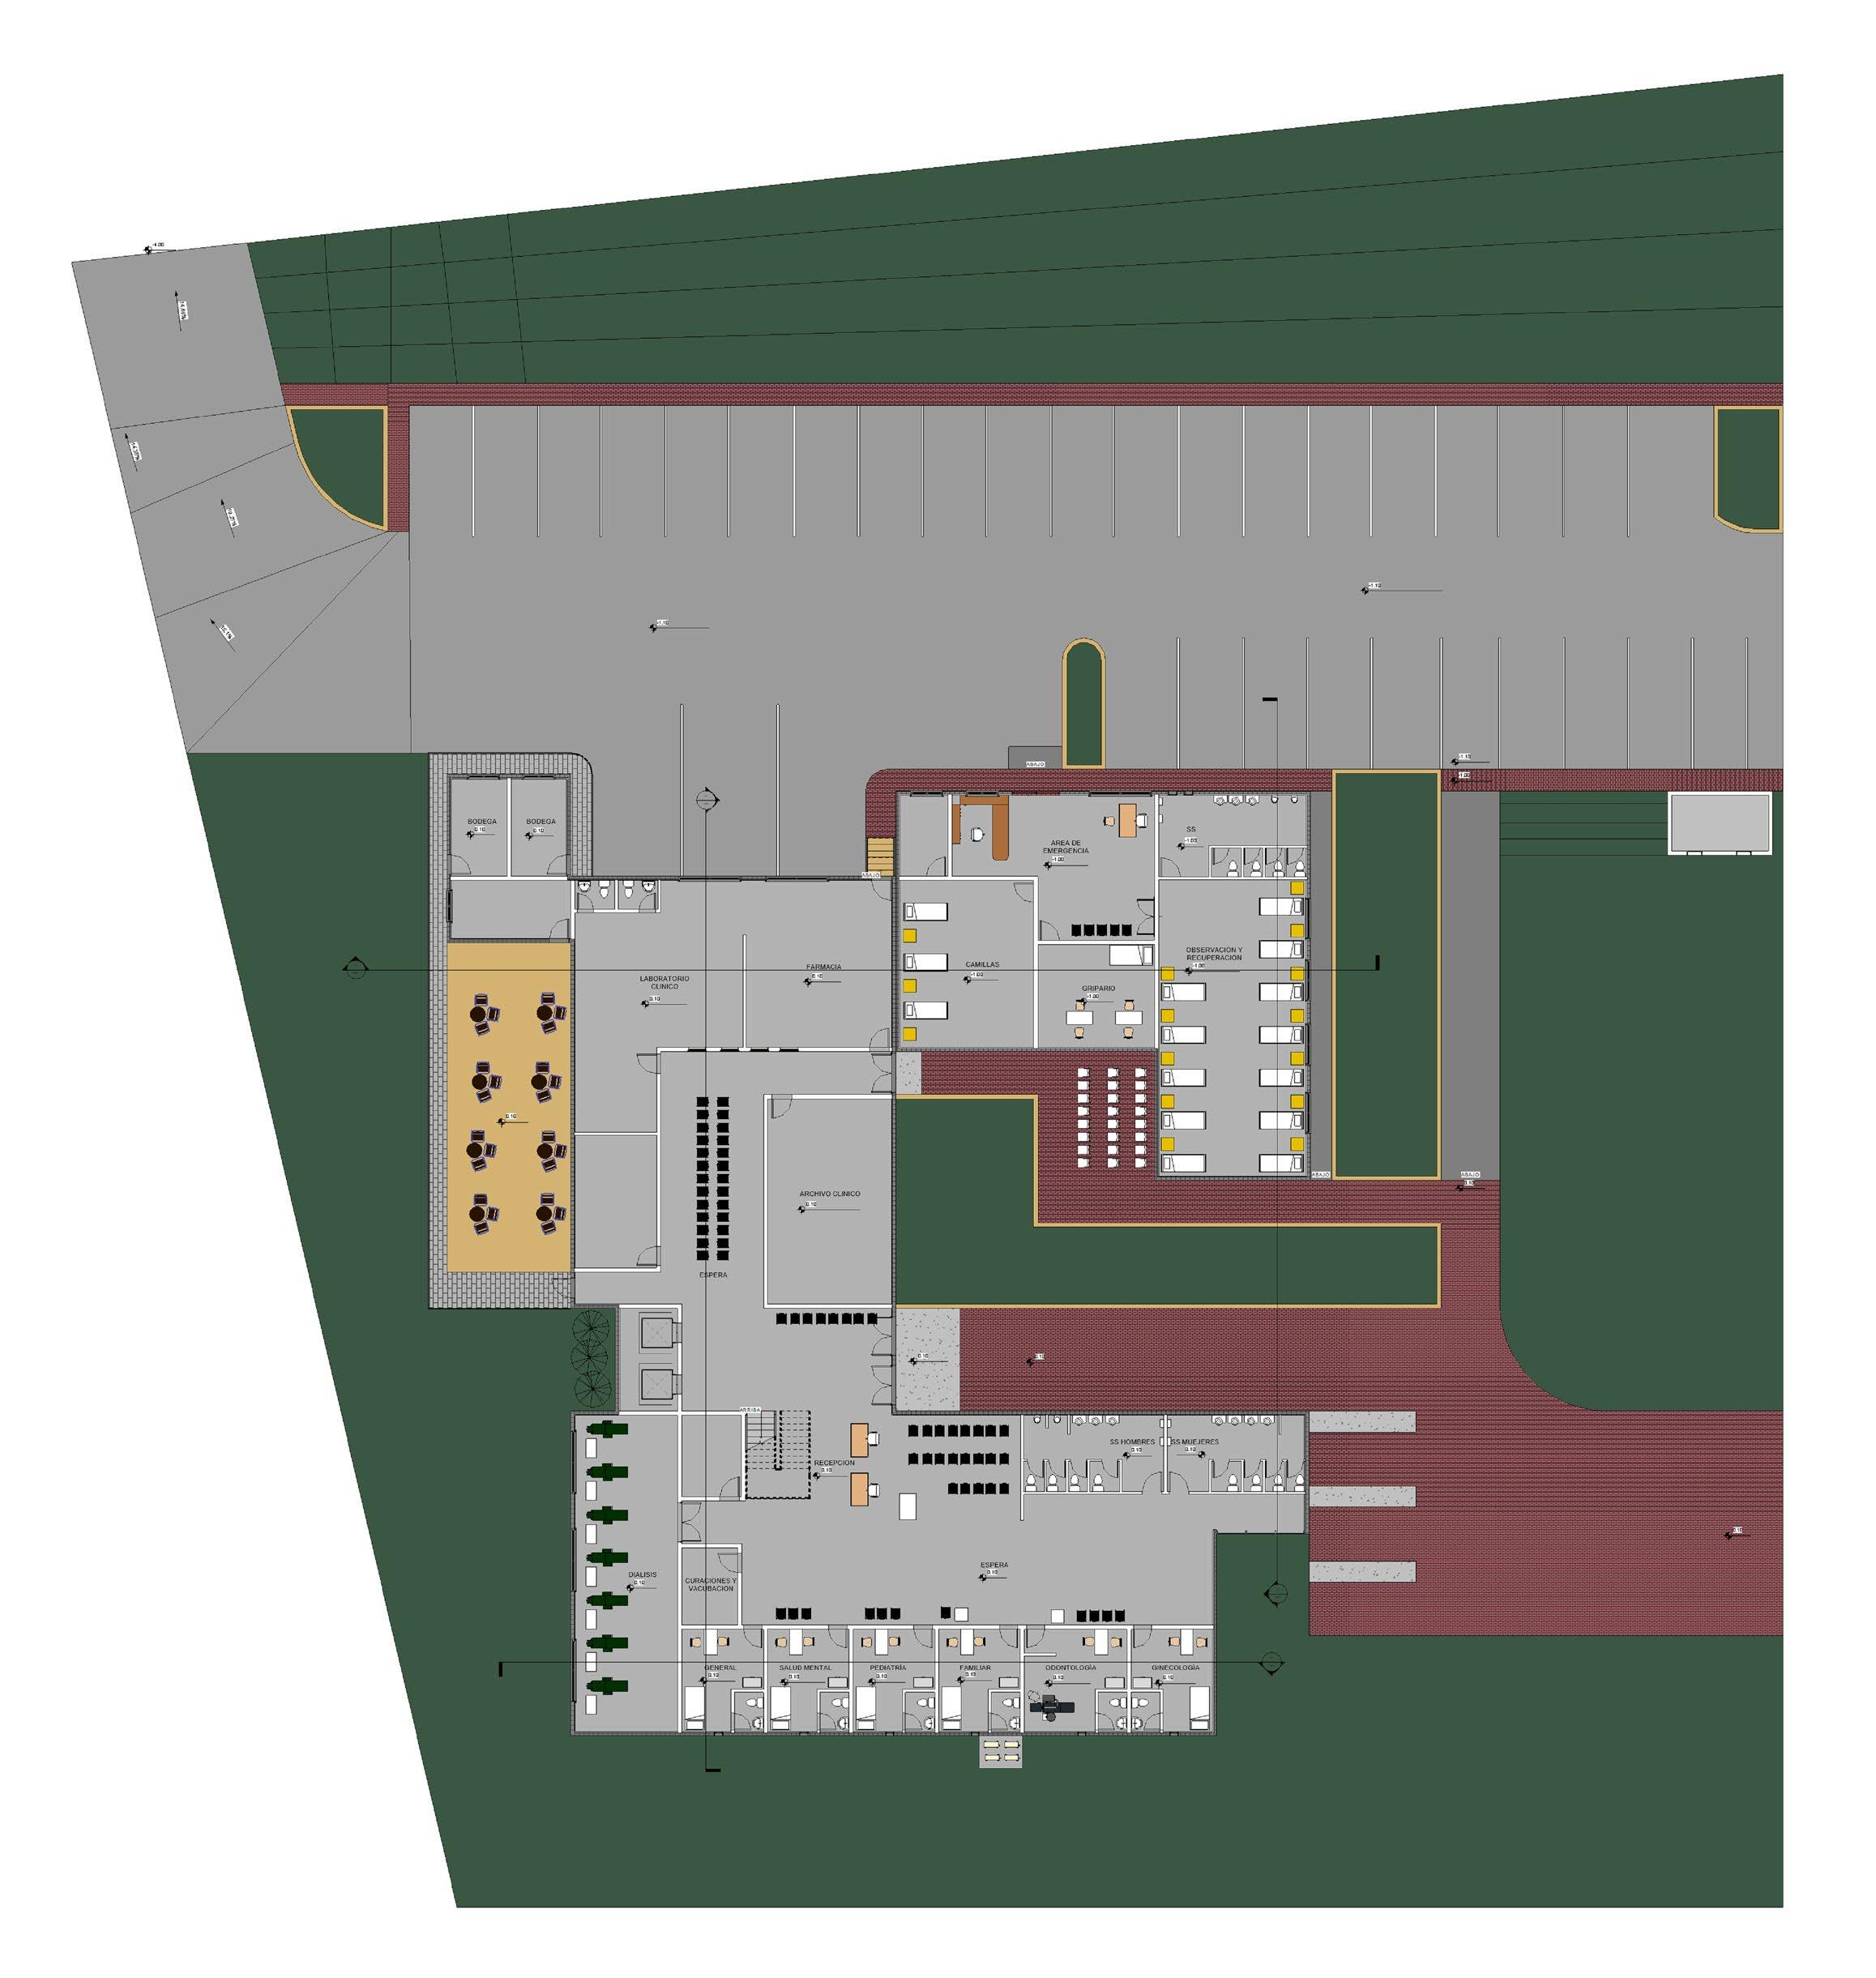

En el primer nivel, a la altura de la calle Azcunaga se encuentran la recepción, los consultorios, el gripario y a la altura de la 4ª Calle Poniente el estacionamiento y la área de emergencia, donde la ambulancias tienen un mejor acceso y salida para atender las emergencias.

En el segundo nivel se encuentra el quirofano del centro médico y la zona administrativa.

El acceso del estacionamiento es sobre la 4ª Calle Poniente, la cual está 4m abajo a nivel del Acceso principal.

Este estacionamiento funciona para los doctores y empleados del centro médico, además para los pacientes.

También acá se encuentra el acceso y estacionamiento para las ambulancias, que salen de la zona de emergencias.

El acceso principal, está ubicado sobre la 3ª Av. Norte, la cual está 4m elevado referente a la 4ª Calle Poniente, el acceso es especialmente para peatones, solamente pueden accesar 3 vehiculos, los cuales tienen su plaza de estacionamiento para discapacitados, los demás vehiculos deben accesar por el estacionamiento general.

Para la facilidad de accesibilidad entre el estacionamiento y la entrada principal se ha creado una rampa con un 10% de inclinación, la cual ayuda al acceso de las personas con discapacidad, además de agregar vegetación alrededor para crear un ambiente comfortable.

El acceso y salida de emergencias se encuentra sobre la 4ª Calle Poniente.

Donde las ambulancias tienen mejor accesibilidad desde la Carretera Troncal del Norte, esto para facilitar la salida y entrada de Apopa al Centro Médico.